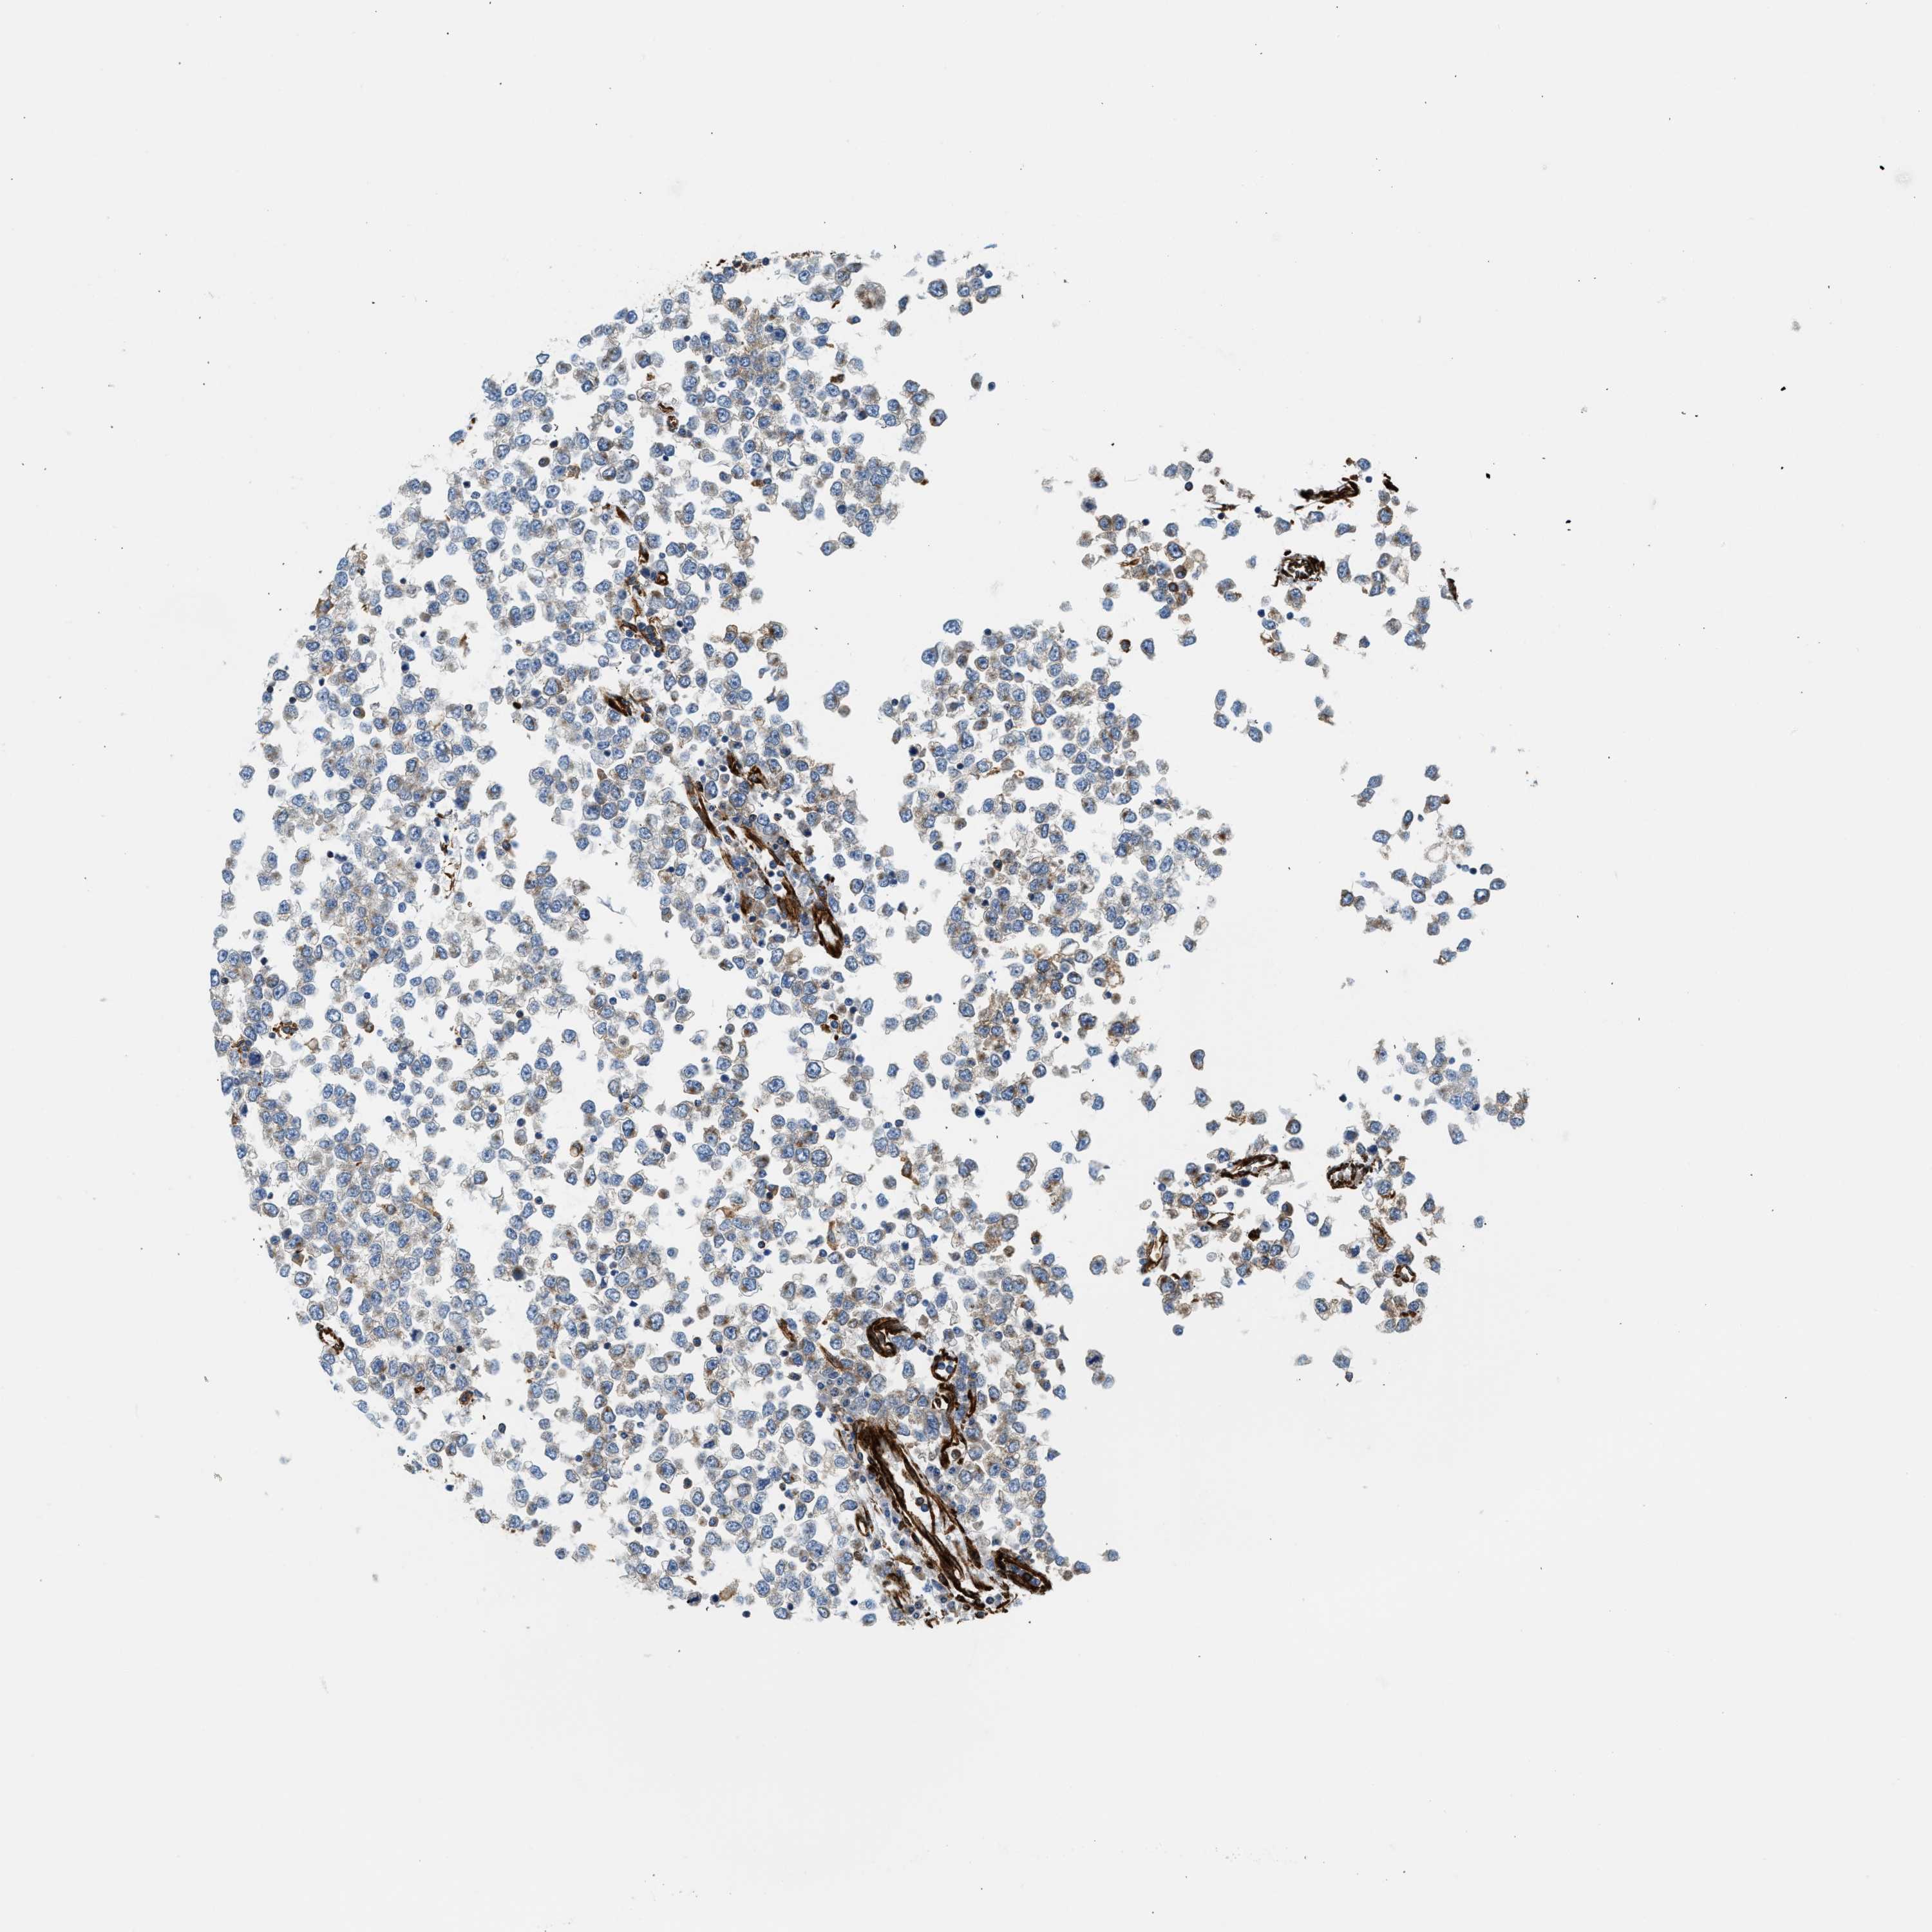

TESTIS CANCER - Protein expressioni

A mouse-over function shows sample information and annotation data. Click on an image to view it in a full screen mode. Samples can be filtered based on level of antibody staining by selecting one or several of the following categories: high, medium, low and not detected. The assay and annotation is described here.

Note that samples used for immunohistochemistry by the Human Protein Atlas do not correspond to samples in the TCGA dataset.

Antibody stainingi

Antibody staining in the annotated cell types in the current human tissue is reported as not detected, low, medium, or high, based on conventional immunohistochemistry profiling in selected tissues. This score is based on the combination of the staining intensity and fraction of stained cells.

Each image is clickable and will lead to virtual microscopy that enables deeper exploration of all samples and also displays staining intensity scores, fraction scores and subcellular localization as well as patient and tissue information for each sample.

Antibody HPA013606

Carcinoma, Embryonal, NOS

Seminoma, NOS